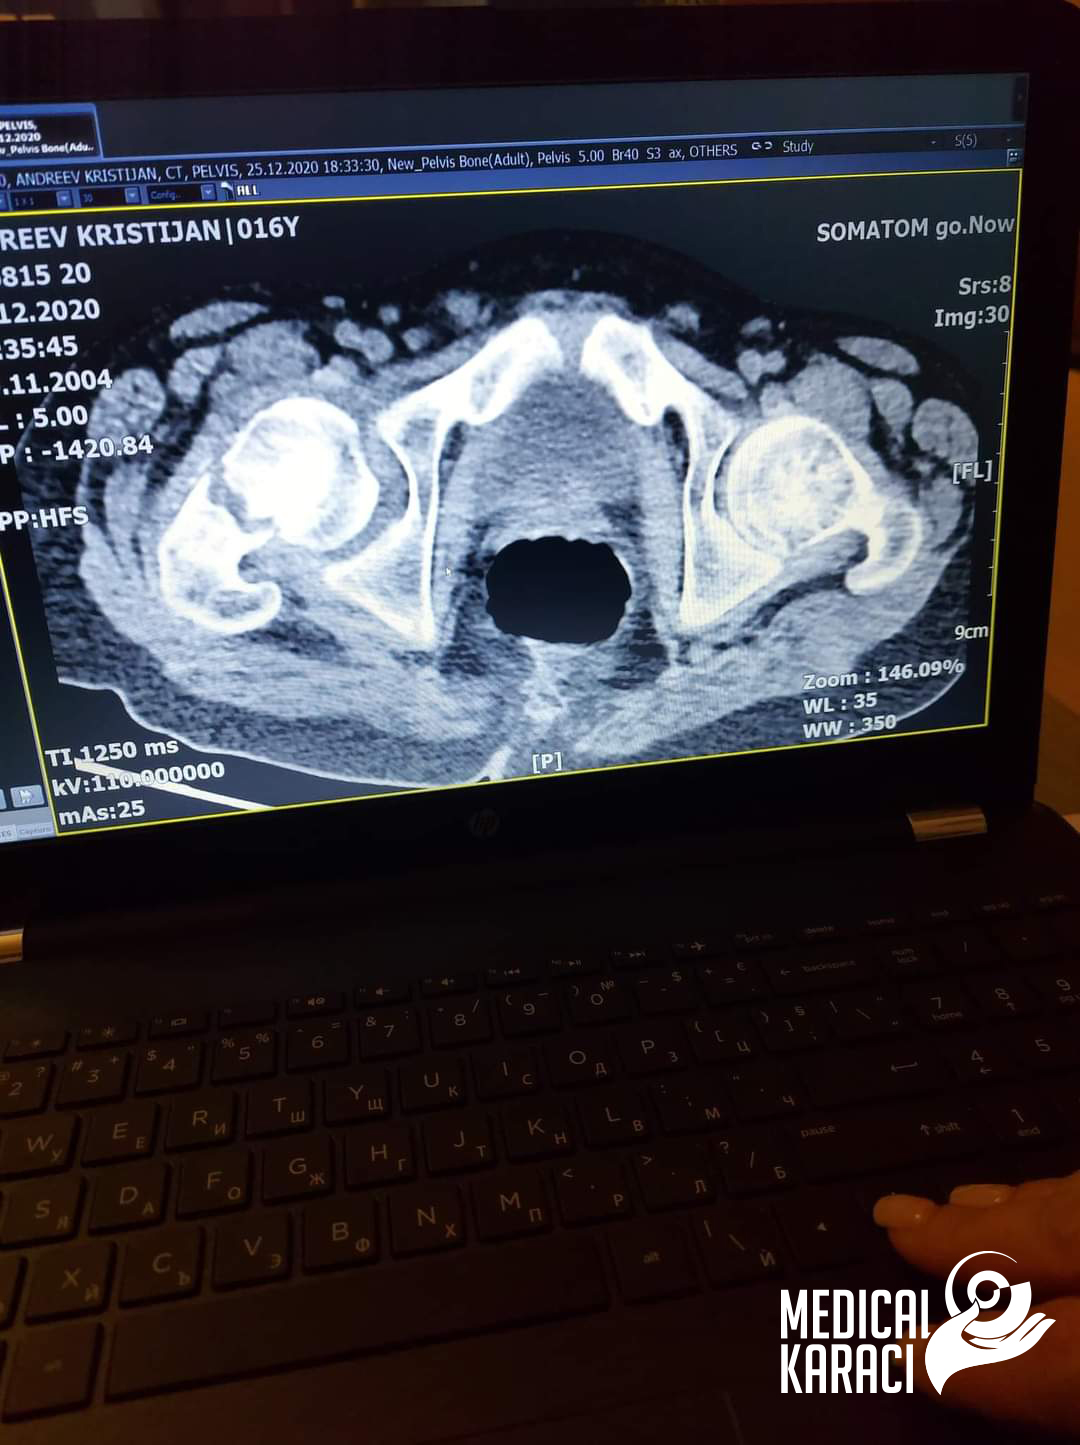

Kristijan 17 yaşında çok ağır bir otizm ve epilepsi hastası bir çocuktur, Aralık 2020'de düşmüş ve vurulmuştur. Makedonya'daki Koga sitesi kazuvaa ni deka nemoze da ho ho operiraat i deka nema nikogash veke da zastane na noge i da odi jas ne se otkazav, no nitu ti mila moja Zvezdelina Kara i Karaci Tours Medical denonokno istrazuvashe, him barashe i him najdobroto za Kristijan !Kristijan blagodarenie na te te i na Prof. Dr. Mustafa Kürklü ZASTANA NA NOZE I ODI 🙏🙏Neznam kako da ti se zablagodaram za se shto napravi i pravish za Kristijan, za celata organizacija vo bolnicata Memorial Bahçelievler Hastanesi Bizimle olduğun her zaman için. Bu yüzden bizimle birlikte seviniyor ve savaşıyorsunuz🙏